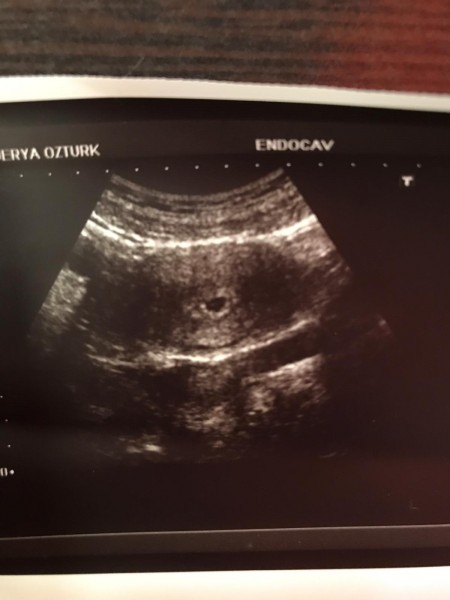

kızlar merhaba cinsiyeti tahmin eder misiniz ❤️❤️

Gebelik haftası 5

Kız bu ne daha bebek yok :) senin daha yol uzun

Evet daha en az 10 haftası var. Ama merak işte bazıları kese şekline göre cinsiyet yorumluyor. Ben inanmıyorum o tarz şeylere. Genital organlar oluşunca ve bebeğin pozisyonu uygunsa Dr zorla söylüyor ki. Ben 23+4 üm hâlâ net değil. Artık detaylıya birşey kalmadı öğrenirim diyorum.

5 haftalık bebek yok ortada sadece kese oluşmuş ne olacağı yada olmayacağı belli değil ve dalga geçer gibi cinsiyetini mi soruyorsunuz hanfendi . Şaka yapıyor olmalısınız !